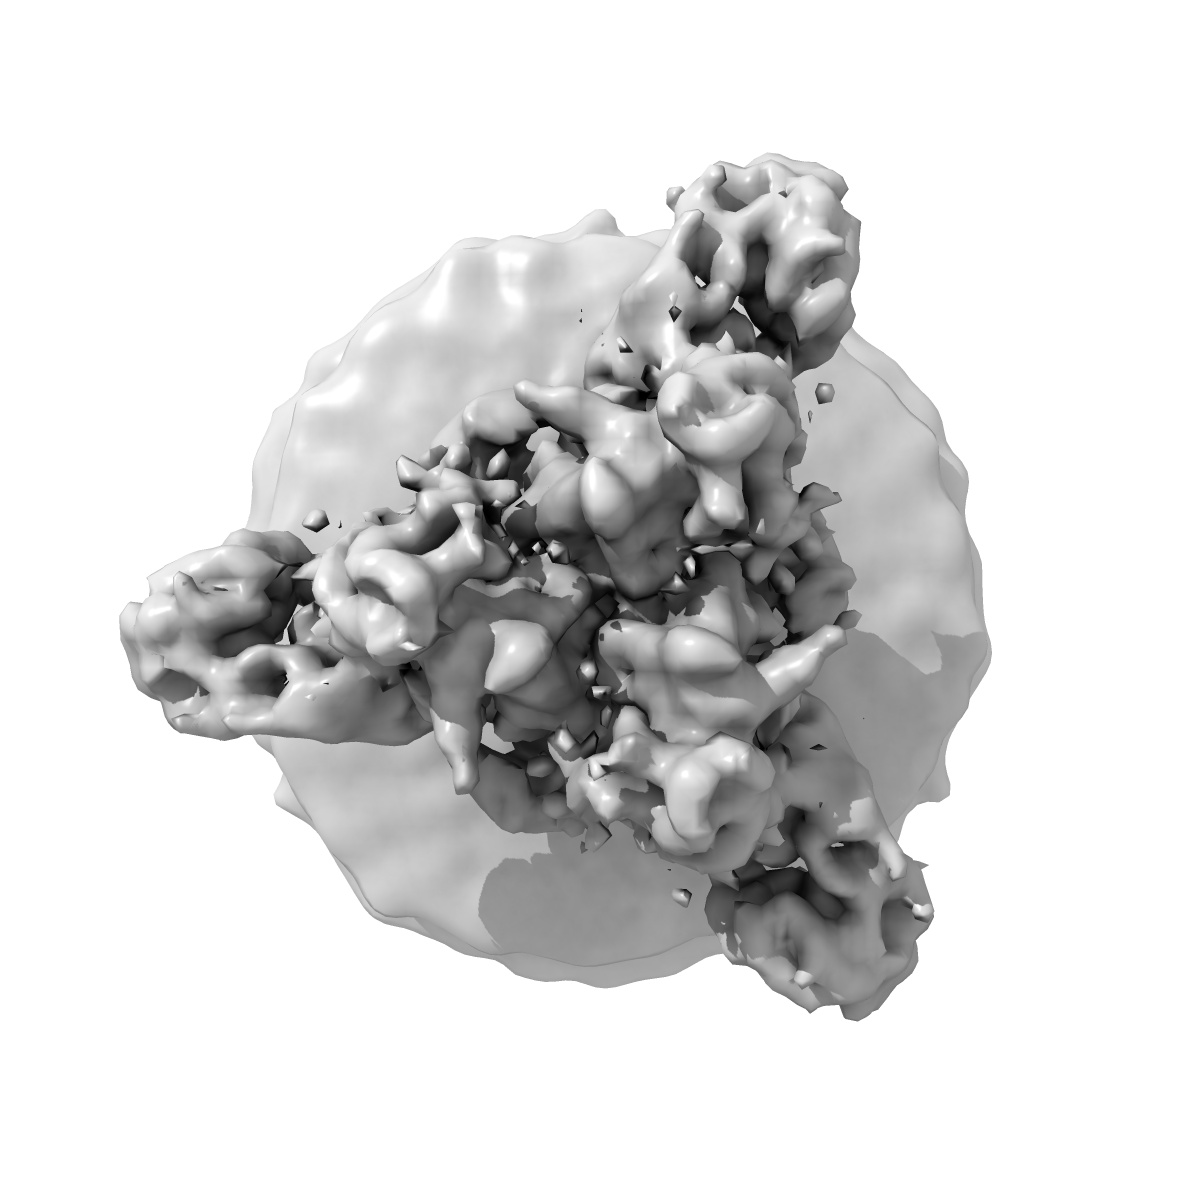

3A6 and KZ52 Fab fragments bound to Ebola GP, subtomogram average from a cylinder mask

Subtomogram averaging9.3 Å

Anti-Ebola virus mAb 3A6 protects highly viremic animals from fatal outcome via binding GP (1,2) in a position elevated from the virion membrane.